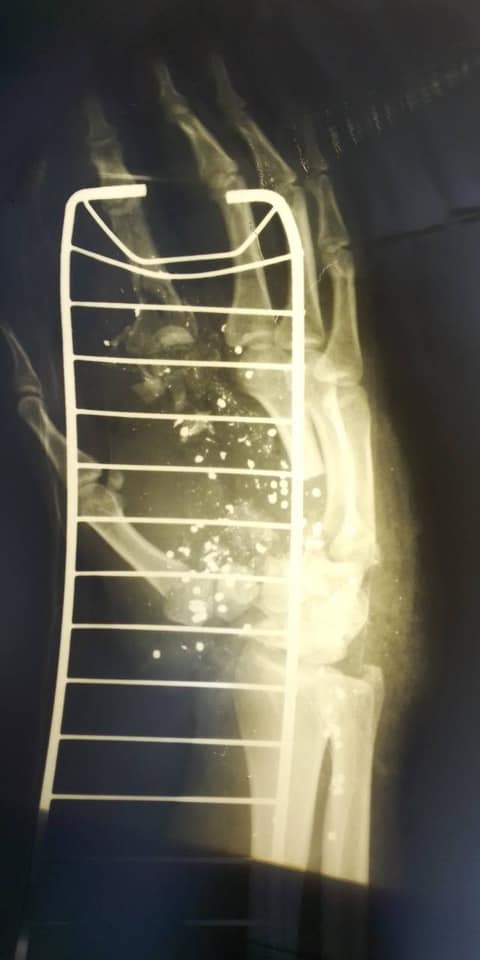

Пострадавший полицейский получил тяжелое ранение руки. Фото: Алексей Билошицкий.

Полицейский, в которого выстрелил Голосеевский стрелок, получил крайне тяжелое ранение руки. Он уже перенес одну операцию, но впереди его ждет длительное лечение.

На данный момент полицейский по имени Сергей находится в клинике имени Шалимова, где хирурги борются за руку парня, практически собирая ее по частям.

Как сообщает глава МВД Украины Антон Геращенко, Сергей работает в полиции два года. Сегодня он получил ранение в следствие выстрела Голосеевского стрелка из охотничьего оружия ружья через дверь.

Согласно прогнозам врачей, если не будет осложнений или нагноений, то существует шанс, что пальцы будут функционировать. Но, к сожалению, рука больше не будет такой, как прежде.

По словам Билошицкого, после этого вызова жизнь парня разделилась на "до" и "после".  Сейчас за руку Сергея борются самые лучшие специалисты клиники имени Шалимова, но впереди его ожидает долгое лечение и реабилитация. При этом результат пока что невозможно спрогнозировать.